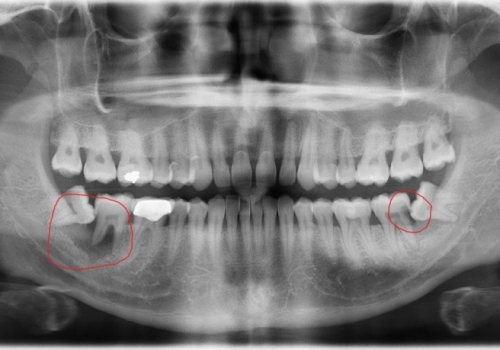

Normal halda insanın diş sırasında hər çənədə iki ədəd olmaqla, ümumilikdə dörd agıl dişi mövcuddur. Ağıl dişinin çıxması bəzi şəxslərdə heç bir kliniki əlamət və ya şikayətə səbəb olmasa da, bir çox hallarda müəyyən kliniki əlamətlərlə öyünü biruzə verir. Bu əlamətlər əsasən çənənin arxa tərəfində təzyiq, çənəni açıb baglama əsnasında agrı və məhdudlaşma kimi özünü göstərə bilir. Bu hallarda mütəxəssis konsultasiyasının önəmi olduqca böyükdür. Belə ki müayinə zamanı cərrah-stomatoloq kliniki və radioloji dəyərləndirmə apararaq dişin dogru pozisiyada yerləşib yerləşmədiyi, dişləmə çıxma ehtimalını, agıl dişinin çənəyə görə ölçüsü və çənə darlıgı kimi durumları dəyərləndirərək tətbiq edilməli olan müalicə taktikasını müəyyən edir.